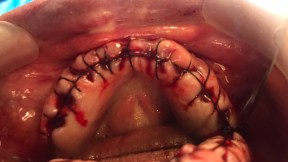

Extractions with Alveoloplasty and Lingual Tori Removal

Upper Left and Upper Right Alveoloplasty